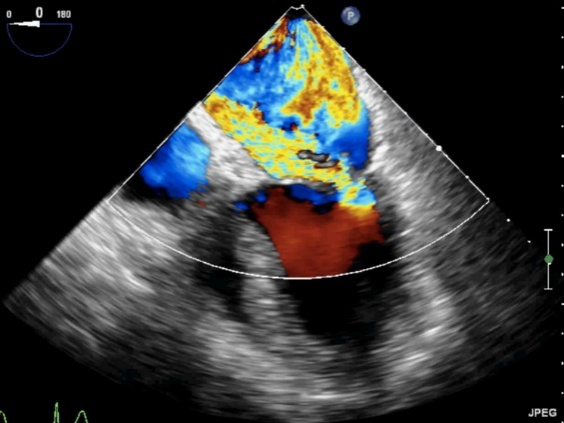

图10 TEE评价二尖瓣形态和功能的基本切面(标注二尖瓣分区)

TEE切面与二尖瓣分区的对应关系可用于二尖瓣脱垂部位的判断,但要注意的是:一定要将2D或3D图像与二尖瓣模型对应起来,不理解切面和模型之间的空间关系,直接用文献上的分区对应实际的超声图像会导致定位不准和交流障碍(图11,12,13,14);另外,经胃底基底段短轴切面对诊断瓣叶裂和穿孔很有帮助,彩色多普勒可以提供有关反流束起源的信息(图14)。

图11四腔心切面显示二尖瓣后叶P2区脱垂

图12 5腔心切面显示二尖瓣前叶A1区脱垂

图13食管中段左室长轴切面显示二尖瓣后叶P2区腱索断裂并脱垂

图14经胃底基底段短轴切面。示二尖瓣前后叶,P3区位于“扇形”的顶点

图21缩流颈的测量食管中段四腔心切面,反流束基底部宽度与二尖瓣反流的严重程度相关。

反流束的方向也很重要,其不仅仅是病因学的线索,也是严重程度的一个征象。中心性反流可由瓣环扩张或心室功能不全引起,偏心性反流(图22)常常由二尖瓣结构本身异常引起的,偏心性的贴壁反流束应该认为是中度以上的。

图22偏心性二尖瓣反流。中食管四腔心切面二尖瓣彩色多普勒血流成像,可见重度MR沿左房内侧壁走行达房顶部。